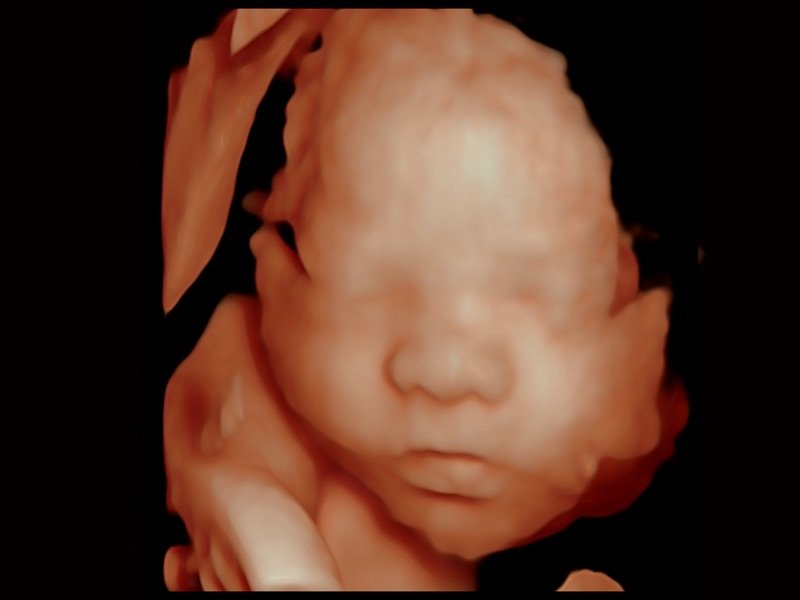

S-Live Silhouette

Durch den Einsatz einer virtuellen Lichtquelle und des Schattierungseffekts sieht S-Live Silhouette durch die Oberfläche hindurch und bildet die Umrisse von Knochen, Organen, Hohlräumen, Gefäßwänden und anderen inneren Strukturen scharf ab. Diese Funktion eignet sich hervorragend zur Erkennung der normalen Anatomie und zur Diagnose komplexer angeborener Fehlbildungen.